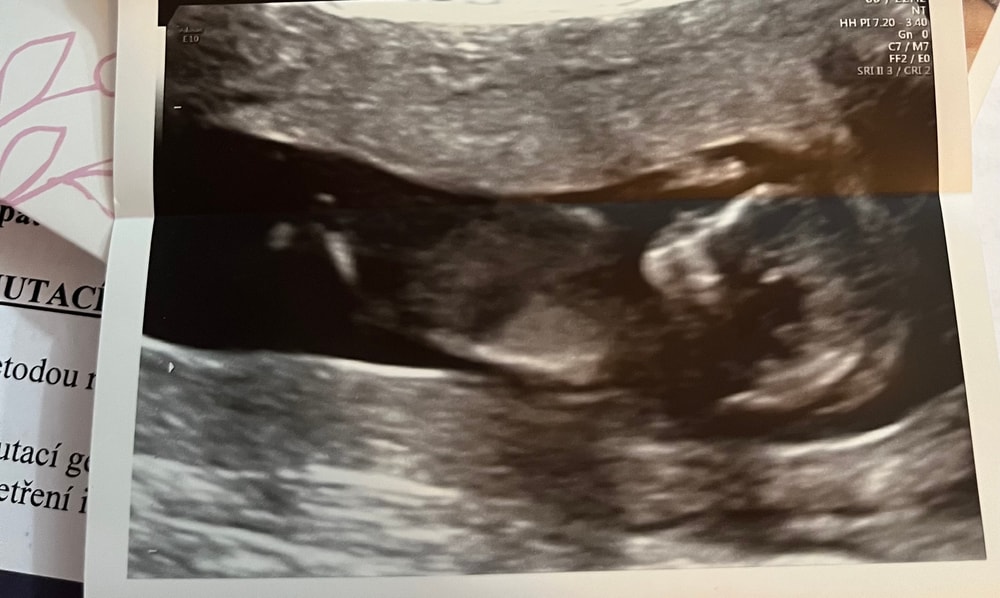

СкринингПервый скрининг позади — волнительный, важный момент.

Слава Богу, с малышом всё хорошо, все параметры в пределах нормы, сердце бьётся, кроха растёт 🙏💛

Сейчас основной вопрос — риск преэклампсии. По результату он составил 1:61, поэтому мне назначили профилактику — препарат для разжижения крови (ацетилсалициловая кислота). Через 4 недели снова на контроль в генетический центр.

Также я сдала кровь на PAPP-A, жду результаты примерно через 10 дней. По синдрому Дауна — низкий риск, 1:4200, это очень хороший показатель. Остальное будет известно чуть позже.